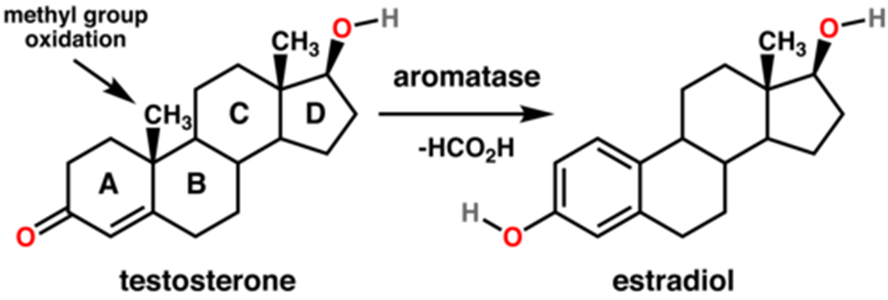

Aromatase Inhibitors have undoubtedly gained an enormous amount of attention within this community, due to studies showing their effectiveness at slowing down epiphyseal closure. They do this by inhibiting the conversion of Testosterone to Estrogen (17-Beta-Estradiol or just Estradiol for short), through the Aromatase Enzyme And this is important because Estrogen closes growth plates by binding to estrogen receptor alpha on chondrocytes, pushing them to mature faster while depleting the reserve of stem-like cells that keep the plates active. However, AIs, at least when used alone, might not be as effective as many people think. Yes, studies proving their effiency exist, that I can't deny. But the extent at which they delay plate closure might just be overblown, with many people misinterpreting them as the "key" to growing forever. However that is simply not the case, and newer studies might just prove that.

Aromatase inhibitors primary function is to delay plate closure, increasing height is an indirect effect of blocking estrogen. This should be common knowledge by now, but their seems to be misconceptions surrounding them. We can likely draw from these studies they work best when used with HGH, not alone. Also another point I wanted to bring up is that i've seen lots of people use them EOD, but that simply isn't optimal. I understand not wanting to oversupress estrogen, but ED mogs in every single way, espically for height. Why? Because EOD causes fluctuations and spikes in estrogen between, remember the aromatase enzyme isn't your body's only way of making estrogen. Other enzymes such as 17β-hydroxysteroid dehydrogenase (17β-HSD) and Steroid Sulfatase (STS), often compensate by upregulating estrogen production. Lastly I want to point out, that many studies, such as study C below, show bone maturation effects are more prominent with consistent use. And the delay effect is around 35-40% vs placebo across many studies, effective yes, but not the key to growing forever JFL . So if you were planning to "cycle" AIs, that likely isn't going to deliever the best results for you.